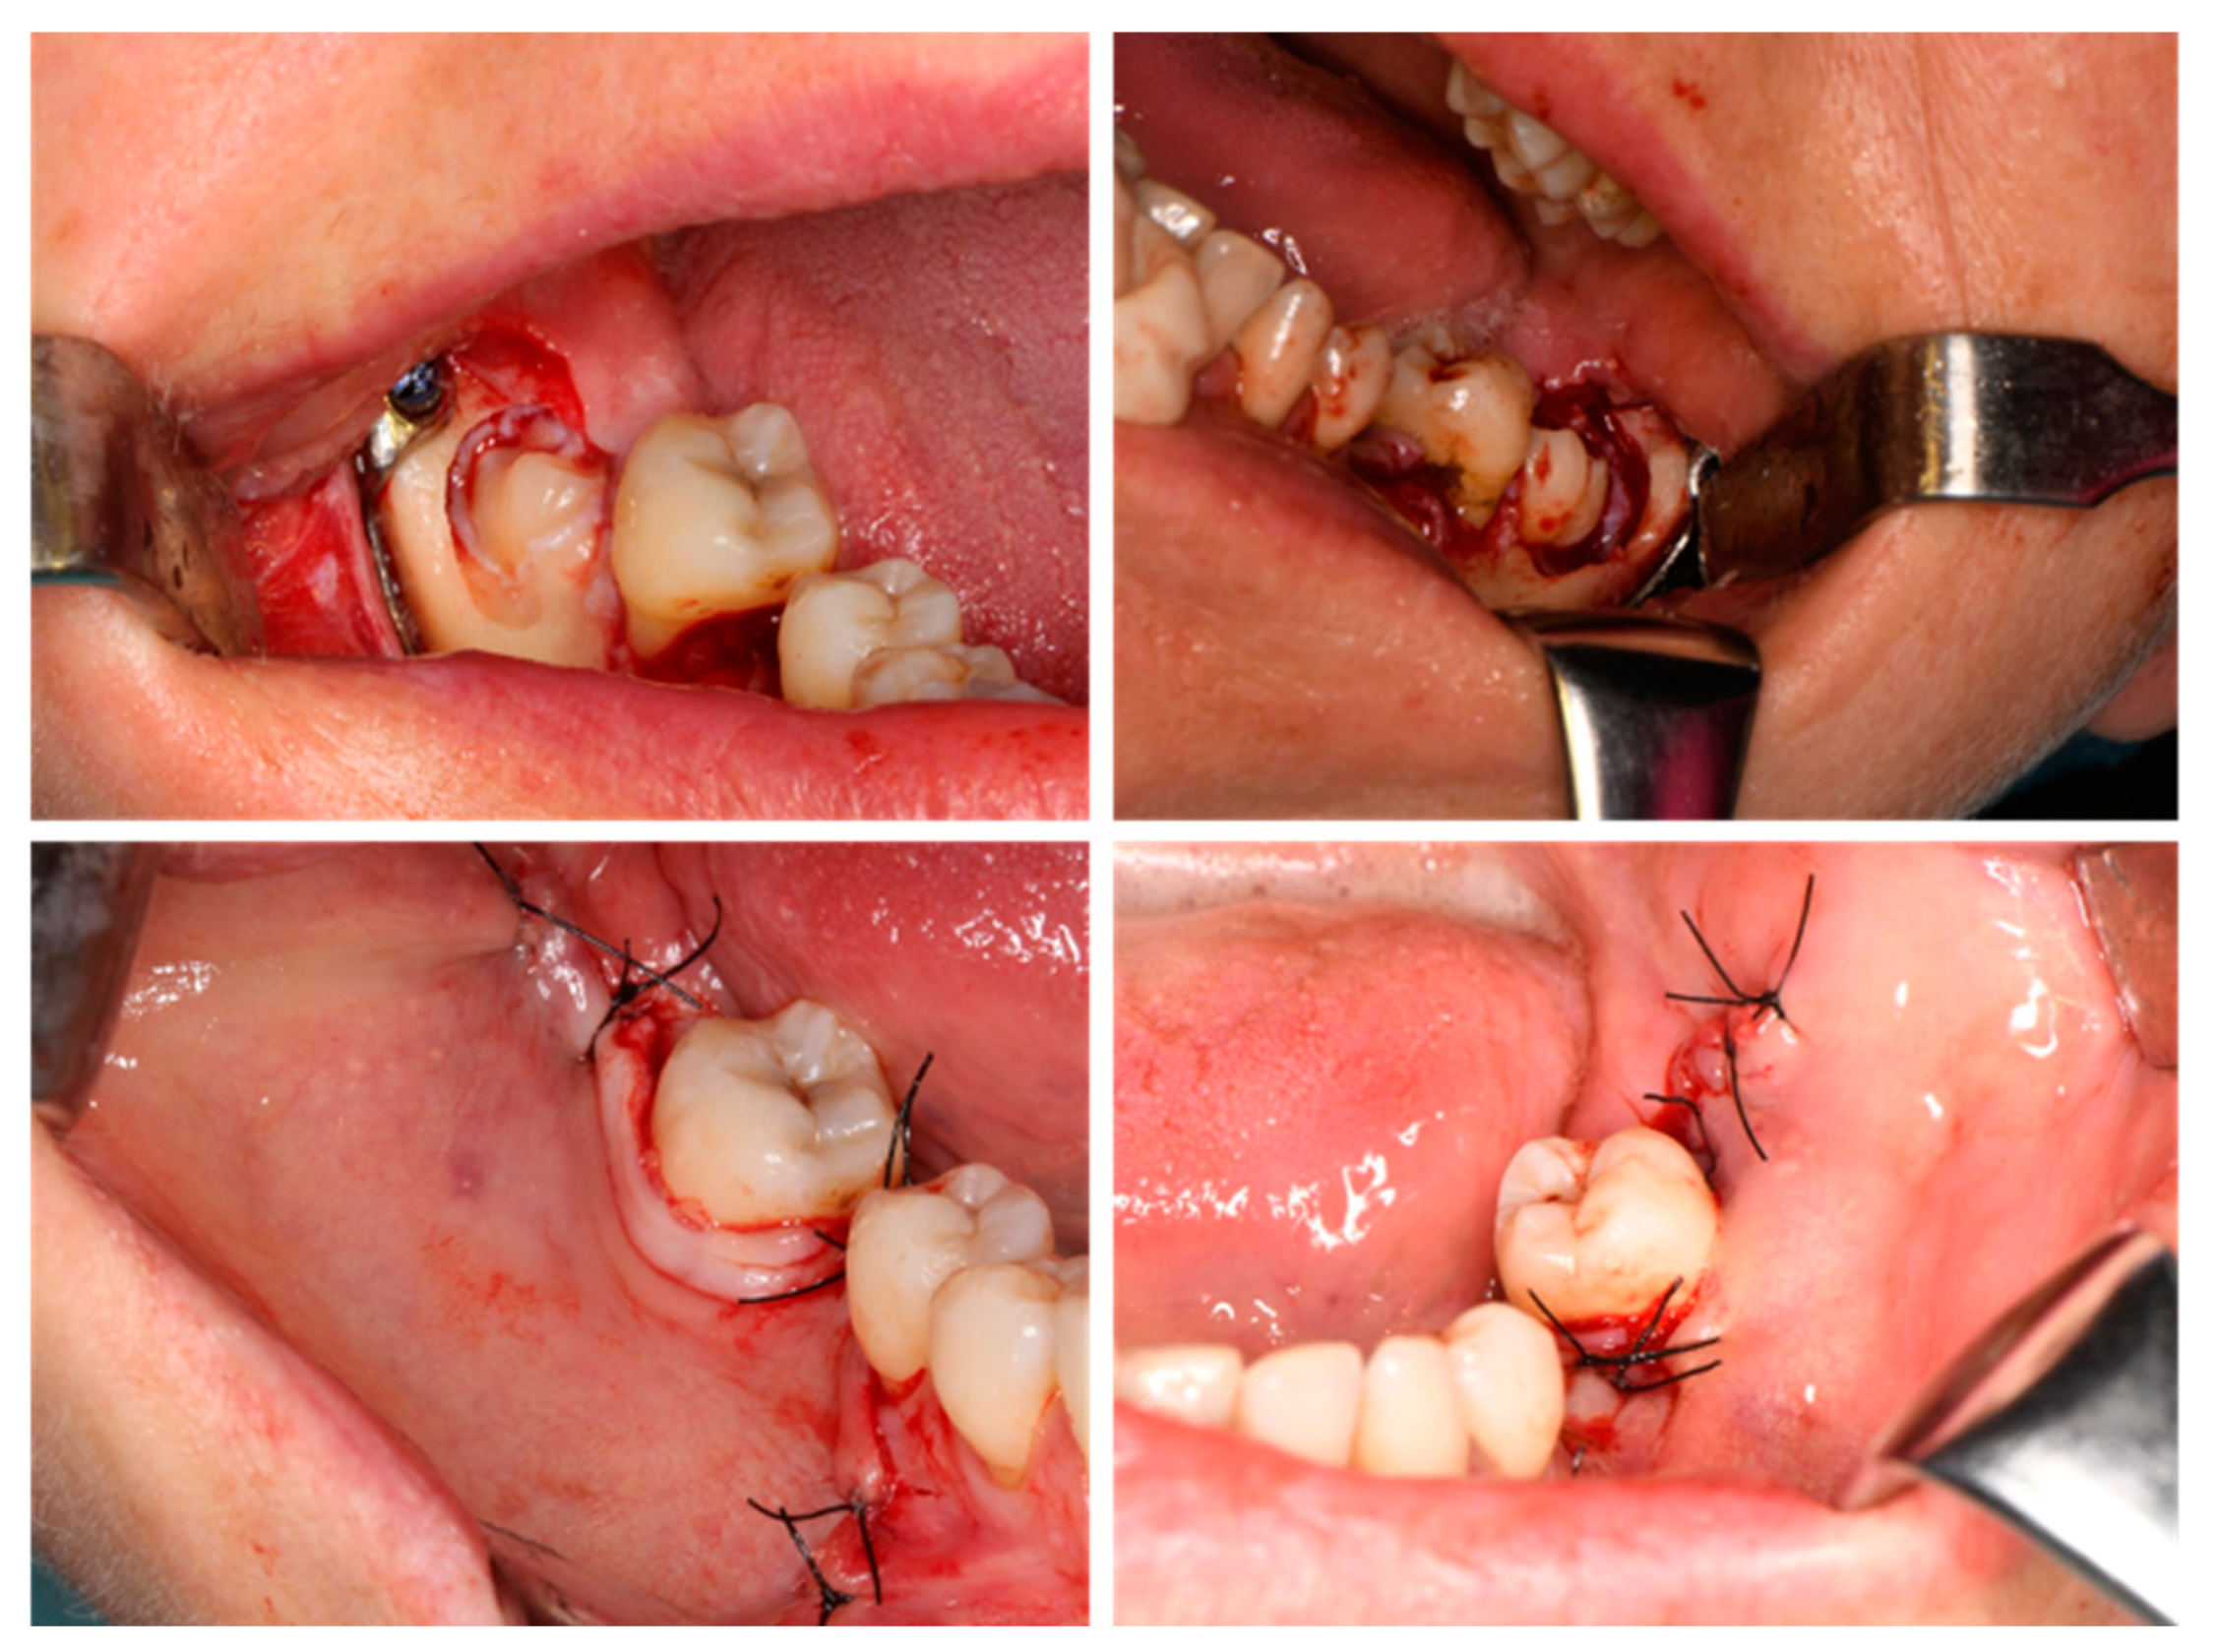

2.4. Surgical Procedure